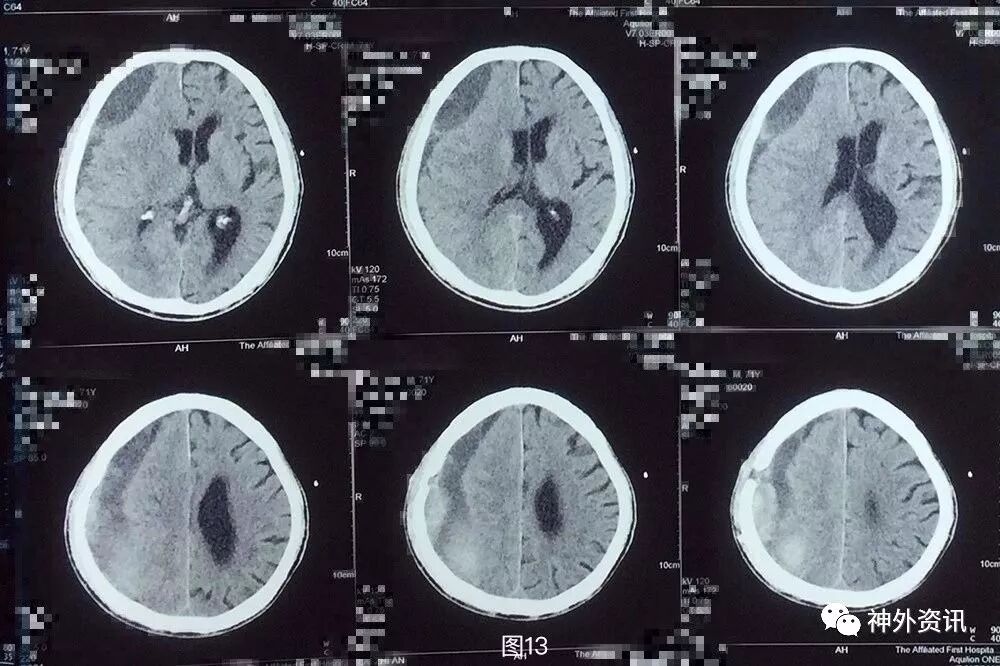

患者,男,71岁,因“ 头部外伤5月,两次钻孔引流术后复发9天 ”入院。

患者5月前不慎头部外伤,当时无黑懵晕厥,无头痛头晕,未重视治疗,3月余前无明显诱因下出现头痛,伴头晕,伴行走不稳,前往外院就诊,查头颅CT示:右侧额颞顶枕部慢性硬膜下血肿考虑(图1),行钻孔引流术。术后复查头颅CT提示右侧额颞顶枕慢性硬膜下血肿钻孔引流术后改变(图2),术后症状好转出院。2月前(术后1月)患者再次出现头痛晕头晕等症状,复查头颅CT:右侧额颞顶枕硬膜下血肿,脑实质受压,中线轻度左偏(图3)。遂再次行右额颞顶枕部硬膜下血肿钻孔引流术,术后患者头痛无明显好转,伴左侧肢体乏力,复查头颅CT见术后局部血肿形成(图4)并进行性增大(图5)。

图1. 外院第1次术前头颅CT提示:右侧额颞顶枕慢性硬膜下血肿考虑。血肿为稍高密度,伴局部高密度。

图3. 外院第2次手术前头颅CT:右侧额颞顶枕硬膜下血肿复发,血肿为稍高密度,脑实质受压,中线轻度左偏。

图4. 第2次手术后1天头颅CT提示:右侧额颞顶枕硬膜下血肿钻孔引流术后再次局部血肿形成。